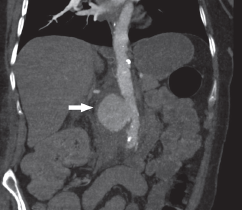

Imágenes y Cirugía

Natalia González Alcolea, María Dolores Chaparro Cabezas, Félix Martínez Arrieta, Victor Sánchez Turrión